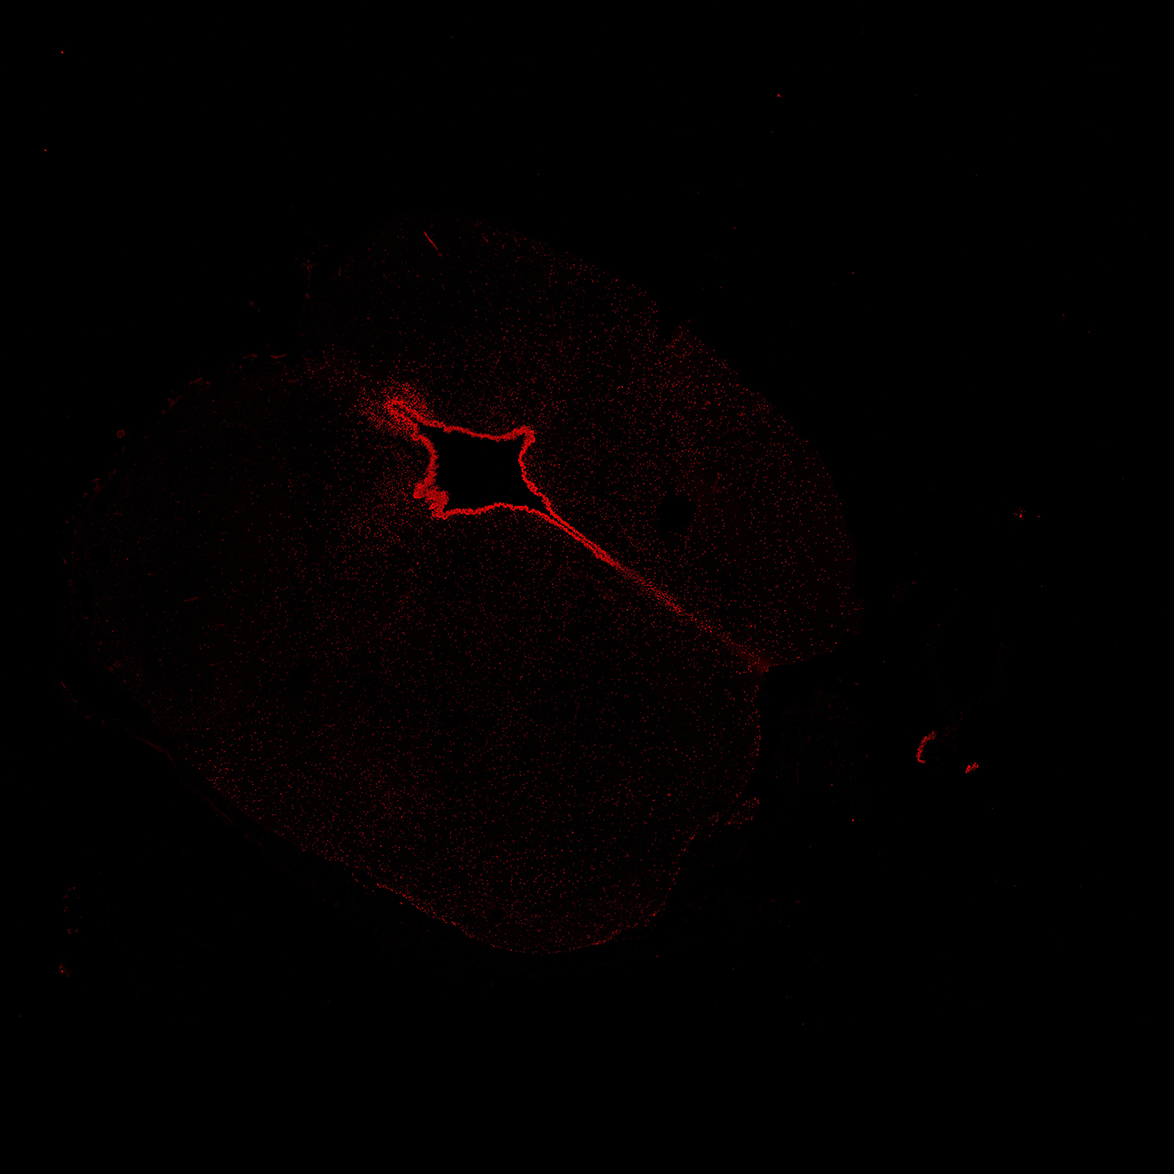

An anatomical analysis of the developing human midbrain from 6 post-conceptional weeks (PCW) to 22 PCW reveals increased tissue complexity, characterized by the emergence of dopaminergic nuclei, as highlighted by immunofluorescence analysis for tyrosine hydroxylase (TH).

TH

7PCW human midbrain

11PCW human midbrain

13PCW human midbrain

15PCW human midbrain

17PCW human midbrain

19PCW human midbrain

22PCW human midbrain